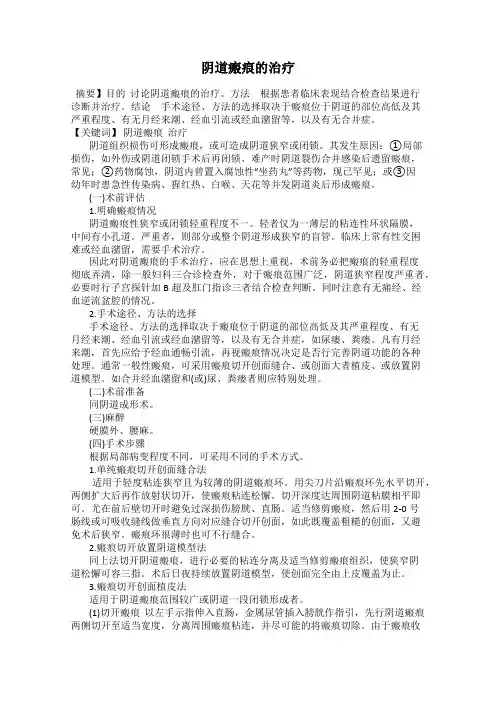

阴道瘢痕的治疗摘要】目的讨论阴道瘢痕的治疗。

方法根据患者临床表现结合检查结果进行诊断并治疗。

结论手术途径、方法的选择取决于瘢痕位于阴道的部位高低及其严重程度、有无月经来潮、经血引流或经血潴留等,以及有无合并症。

【关键词】阴道瘢痕治疗阴道组织损伤可形成瘢痕,或可造成阴道狭窄或闭锁。

其发生原因:①局部损伤,如外伤或阴道闭锁手术后再闭锁、难产时阴道裂伤合并感染后遗留瘢痕,常见;②药物腐蚀,阴道内曾置入腐蚀性“坐药丸”等药物,现已罕见;或③因幼年时患急性传染病、猩红热、白喉、天花等并发阴道炎后形成瘢痕。

(一)术前评估1.明确瘢痕情况阴道瘢痕性狭窄或闭锁轻重程度不一。

轻者仅为一薄层的粘连性环状隔膜,中间有小孔道。

严重者,则部分或整个阴道形成狭窄的盲管。

临床上常有性交困难或经血潴留,需要手术治疗。

因此对阴道瘢痕的手术治疗,应在思想上重视,术前务必把瘢痕的轻重程度彻底弄清,除一般妇科三合诊检查外,对于瘢痕范围广泛,阴道狭窄程度严重者,必要时行子宫探针加B超及肛门指诊三者结合检查判断。

同时注意有无痛经、经血逆流盆腔的情况。

2.手术途径、方法的选择手术途径、方法的选择取决于瘢痕位于阴道的部位高低及其严重程度、有无月经来潮、经血引流或经血潴留等,以及有无合并症,如尿瘘、粪瘘。

凡有月经来潮,首先应给予经血通畅引流,再视瘢痕情况决定是否行完善阴道功能的各种处理。

通常一般性瘢痕,可采用瘢痕切开创面缝合、或创面大者植皮、或放置阴道模型。

如合并经血潴留和(或)尿、粪瘘者则应特别处理。

(二)术前准备同阴道成形术。

(三)麻醉硬膜外、腰麻。

(四)手术步骤根据局部病变程度不同,可采用不同的手术方式。

1.单纯瘢痕切开创面缝合法适用于轻度粘连狭窄且为较薄的阴道瘢痕环。

用尖刀片沿瘢痕环先水平切开,两侧扩大后再作放射状切开,使瘢痕粘连松懈。

切开深度达周围阴道粘膜相平即可。

尤在前后壁切开时避免过深损伤膀胱、直肠。

适当修剪瘢痕,然后用2-0号肠线或可吸收缝线做垂直方向对应缝合切开创面,如此既覆盖粗糙的创面,又避免术后狭窄。

疤痕的治疗方法有哪些?疤痕治疗的方法非常多,在医学上一般分为非手术治疗、手术治疗、综合治疗。